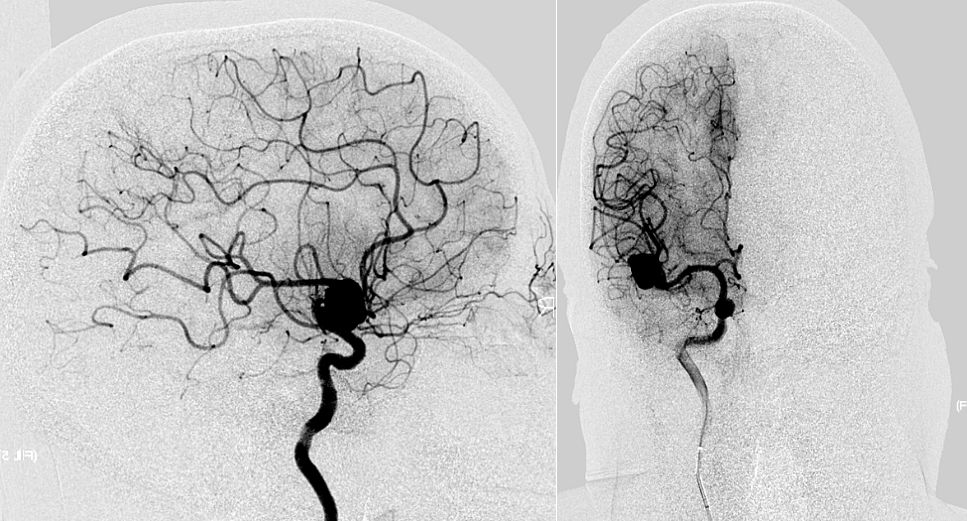

cta排查颅内动脉瘤的局限,dsa才是金标准!

何升学副主任医师三例大脑中动脉瘤病例分享